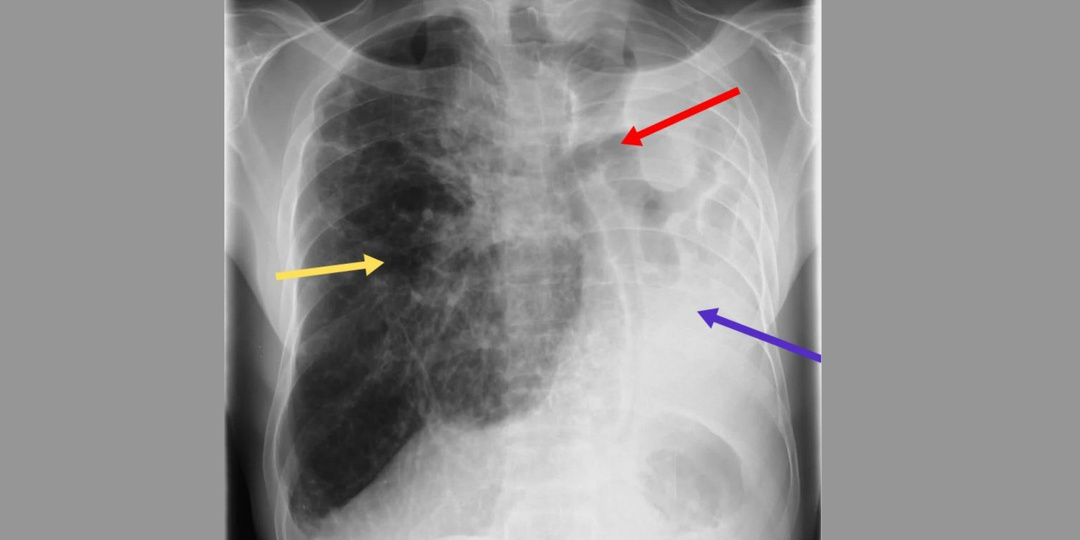

Дайджест интересных клинических случаев марта

Разрушение легкого туберкулезной этиологии, амнезия из-за рака без структурных поражений мозга, метастазирование опухоли яичника спустя 25 лет ремиссии и другое — в подборке интересных клинических случаев прошедшего месяца. Мужчина в возрасте 41 года с сахарным диабетом 2-го типа, артериальной гипертензией (АГ) и ишемической болезнью сердца (ИБС) поступил в отделение неотложной помощи через неделю после уретероскопии и лазерной литотрипсии по поводу камня в правом мочеточнике. Пациент жаловался на сильную боль в спине, тошноту и рвоту. Боль иррадиировала в обе нижние конечности и сопровождалась значительной слабостью в обеих ногах. Пациент отрицал травмы, лихорадку, дизурию или гематурию. При осмотре: ЧСС 130 уд./мин., артериальное давление 150/90 мм рт. ст., сатурация кислорода 98%, ЧДД 20 циклов/мин., температура 36°C, цианоз обеих нижних конечностей. На ЭКГ — синусовая тахикардия. Уровень креатинфосфокиназы составил 58 155 МЕ/л, а уровень лактатдегидрогеназы — 1793 МЕ/л. Остальные п